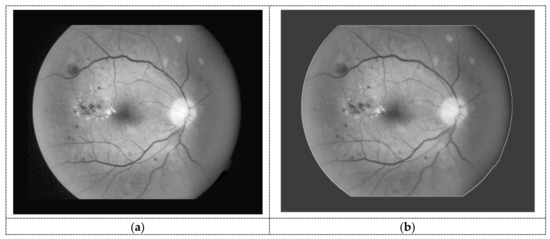

2.2.2. Segmentation Stage

Hand-Crafted Image

Seed Points of the Hemorrhage Candidates

Smart Window-Based Adaptive Thresholding for Segmentation (SWAT)

3.2. Segmentation Result